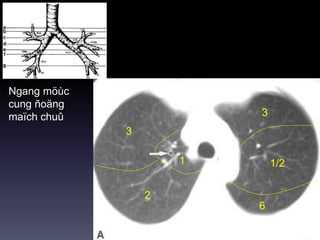

Ngang möùc

cung ñoäng

maïch chuû

3

2

1/21

6

Möùc Carina

1/2